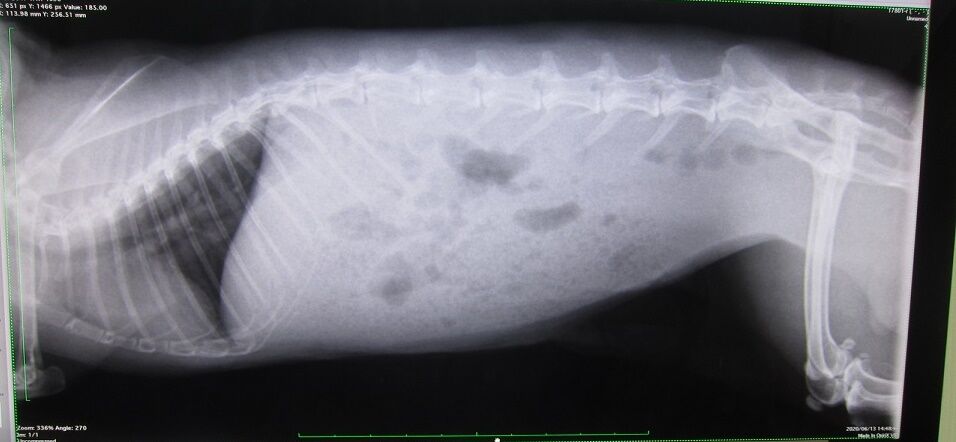

はい、もしや痩せたとか?って体重測定の比較です、

もしかして、いわゆる幼少期からの成長の変化なのかも…

ってことは、思ってるよりも相当若いかもしれませんね。